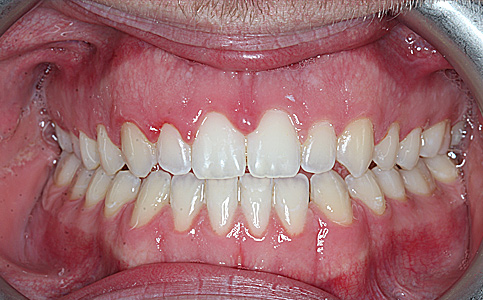

Pacjent zgłosił się z powodu niezadowalającego koloru i kształtu zębów, nie chciał także szlifować swoich zębów pod licówki/korony. Odpowiedzią na jego potrzeby był BONDING czyli estetyczna odbudowa kompozytowa. Przed wykonaniem BONDINGU pacjent był zdeprogramowany aby ustawić staw skroniowo-żuchwowy w dobrej i wygodnej pozycji, zostały odbudowane zęby tylne do kształtów anatomicznych oraz podniesienie w zgryzie aby móc estetycznie przedłużyć zęby przednie. Efekt leczenia sprawił że Pacjent opuścił nasze Centrum stomatologii i Ortodoncji z szerokim uśmiechem.